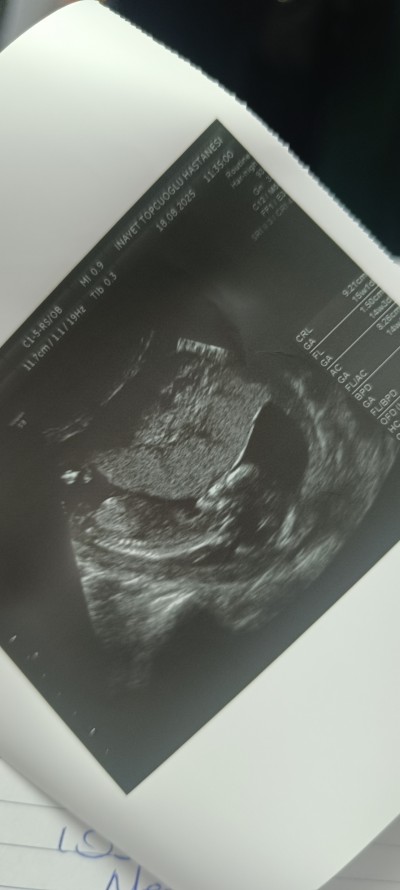

14 +3 haftalık bebeğim ultrasondan anlayan anneler tahmin edebilirmisiniz iki oğlum var önceligim tabiki hayırlı sağlıklı evlat olsun ama merak ediyorum:)

Gebelik haftası 14+6